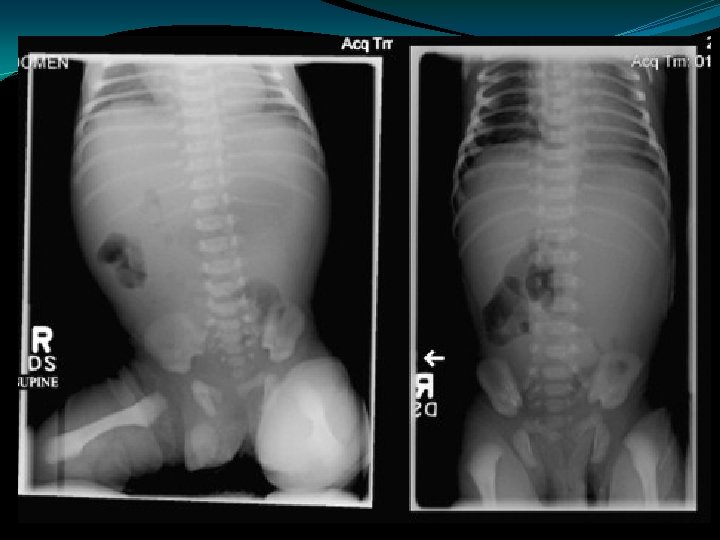

In Utero Perforation �Caused by obstruction: �Meconium Ileus �Hirschprungs �Volvulus �Early perforation leads to Ca++ deposits �Later perforation may cause ascites, no Ca++ �Adhesions lead to obstruction

Meconium Ileus �Usually a manifestation of cystic fibrosis � 20% of infants with CF present with mec ileus �Obstruction of proximal ileum by thick, sticky round meconium pellets �Absence of air fluid levels �“soap bubbles” �Complications: �perforation, peritonitis, pseudocyst, ileal atresia/stenosis

Meconium Ileus �Contrast enema: �Small colon �Filled with pellet-like meconium when contrast extends to IC valve �Contrast can wash out the obstructing plugs and meconium plugs �The diagnosis of CF should be ruled-out